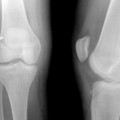

Rehabilitation after anterior cruciate ligament (ACL) reconstruction has evolved over the past 20 years and continues to advance rapidly. The evolution in rehabilitation after ACL reconstruction is in part a result of the development of different surgical procedures that address ACL injuries. In particular, recent efforts to anatomically reconstruct the ACL, which is defined as the functional restoration of the ACL to its native dimensions, collagen orientation, and insertion sites1 is an important consideration for postoperative rehabilitation. Anatomic ACL reconstruction may result in a more rapid return of range of motion (ROM); however, the in situ forces in an anatomically placed graft are greater (comparable with the native ACL) than those in a nonanatomically placed graft (less force than the native ACL as a result of nonanatomic position of the graft).2 As a result, rehabilitation and return to sport after anatomic ACL reconstruction may need to be progressed slower than after traditional, nonanatomic ACL reconstruction.